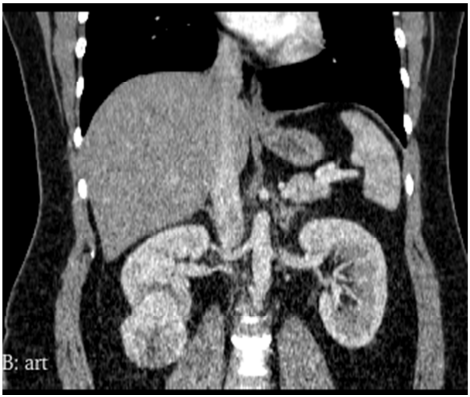

Homem de 56 anos de idade, hipertenso, diabético realizou tomografia de abdome, que demonstrou uma massa renal sólida, incidental, hipervascular, com 5,3 cm de diâmetro, no polo inferior do rim direito, distando 0,5 cm da via excretora. Qual a conduta mais adequada?